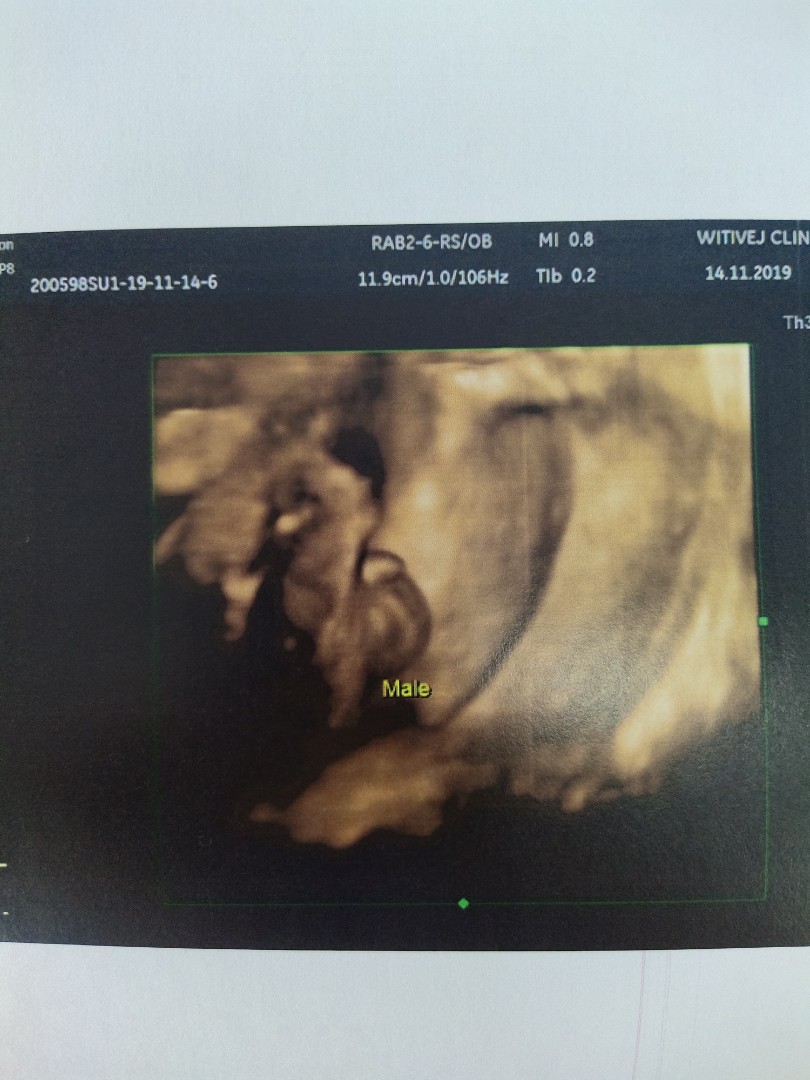

บ้านนี้กำหนดคลอด 28 มีนา ลูกชายครับ แม่ๆคลอดวันไหนกันบ้างคะ ได้ลูกชายหรือลูกสาว ขอให้แม่ๆทุกๆคนคลอดง่ายๆ แข็งแรงปลอดภัยกันทั้งคุณแม่และลูกทุกๆคนนะคะ